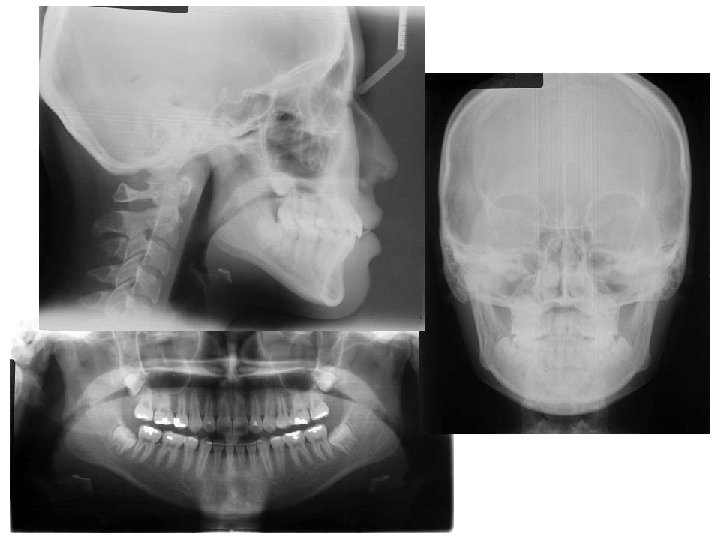

Initial Panoramic Radiograph

Initial PA Cephalogram Mx width Mn width Difference ANS-Me 68 mm 90 mm 22

Initial PA Cephalogram Mx width Mn width Difference ANS-Me 68 mm 90 mm 22 mm 0º

Initial Lateral Cephalogram